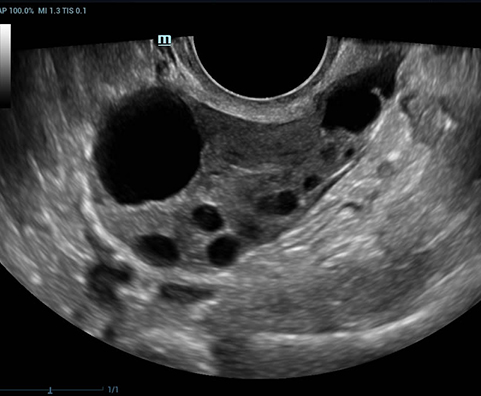

Selain kualitas gambar premium, Resona 7 juga meningkatkan kemampuan penelitian klinis dengan V Flow revolusioner untuk evaluasi hemodinamika vaskular, serta pengambilan penampang tercanggih dari rangkaian data 3D untuk diagnosis CNS pada janin. Kombinasi pengoperasian multisentuh berbasis gerakan yang paling intuitif dengan semua fitur klinis penting membuat Resona 7 menjadi gebrakan baru dalam inovasi ultrasound.